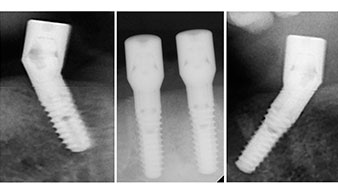

Zur Planung und Risikominimierung wurde eine dreidimensionale Volumentomografie (DVT, Planmeca) erstellt. Dieses zeigte, dass die Qualität und Quantität des Knochens für eine Operation und Sofortversorgung nach der Fast & Fixed-Methode ausreichend war. Nach Protokoll dieses Konzeptes wird in Regio 35, 32, 42 und 45 implantiert. Durch die bis zu 45-Grad-Schiefstellung der distalen Implantate wird das Durchtrittsprofil nach posterior verlegt und ein größeres Stützpolygon erreicht (Abb. 3).

Fast & Fixed-Methode

Abb. 3

Das chirurgische Protokoll der verwendeten Implantate (SKY, bredent medical) schreibt eine Umdrehungszahl von 1.200/min für die Pilotbohrungen vor (Abb. 7–9).

Abb. 7

Umdrehungszahl von 1.200/min

Abb. 8

Abb. 9

Dies entspricht der nächsten Position der Voreinstellung am Implantmed. Zu erkennen ist die etwa 45-Grad-Schräghaltung des W&H Winkelstückes nach mesiokaudal in Regio 45, um den Nervus mentalis zu schonen. Das Foramen mentale gilt als anatomische Orientierung für alle Bohrungen in diesem Bereich. Die anschließenden Bohrungen werden mit einer reduzierten Umdrehungszahl von 300/min durchgeführt (Abb. 10 und 11).